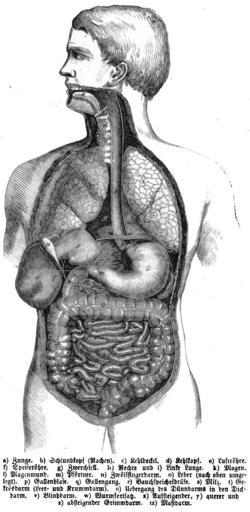

| View Original: | Die_Gartenlaube_(1860)_b_104.jpg (515x1054) | |||

| Keywords: Die Gartenlaube (1860) b 104.jpg Die_Gartenlaube_ 1860 _104 jpg Die_Gartenlaube_ 1860 _105 jpg Historic anatomical plates and drawings Anatomical plates and drawings of the human torso | ||||